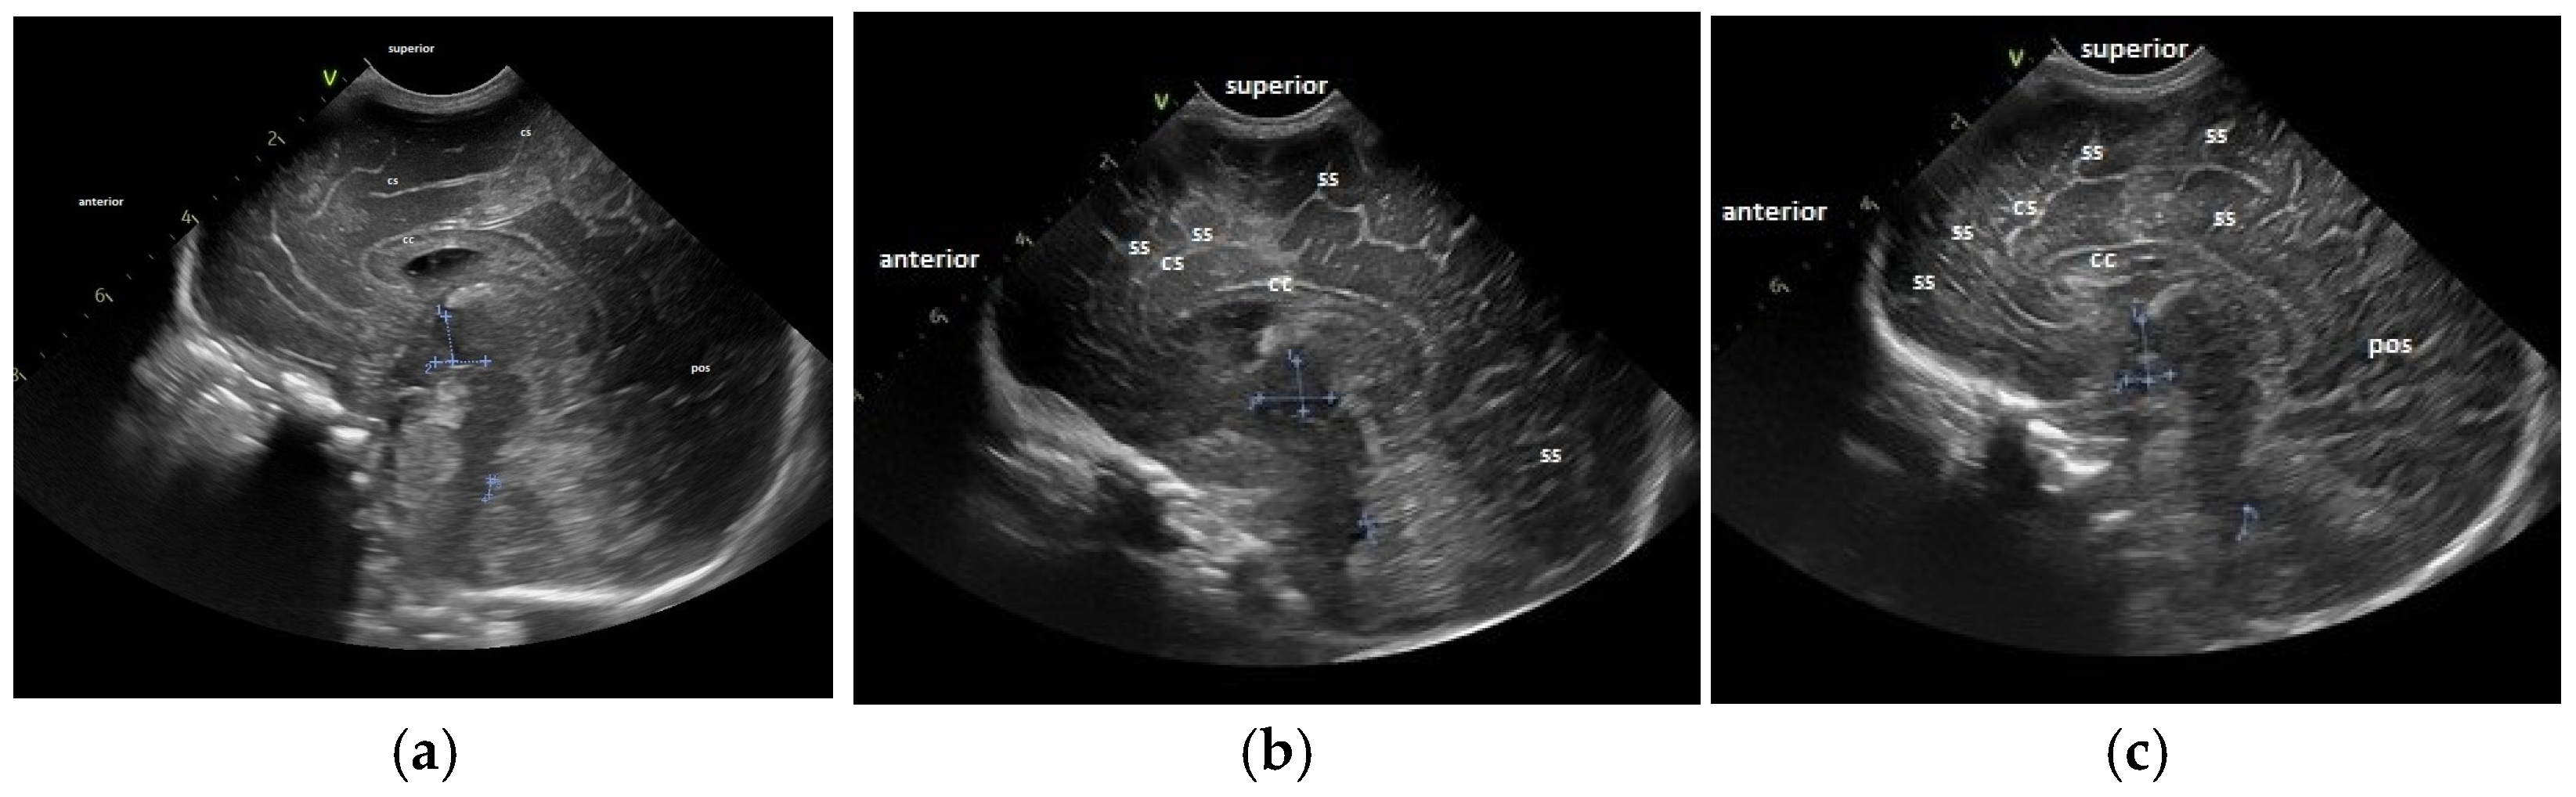

- The gyral maturation pattern—evaluated in 3 sections—coronal at the level of the foramen of Moro—looking at the Sylvian fissure and the depth of the sulci: sagittal—looking at the frontal gyri and sulci and the presence of the central/marginal sulcus and parasagittal, temporal, at the level of the insula [39]. The cortical gyral maturation was assessed according to previously published scores [15,20], and to know patterns of sulcal and gyral maturation [21,22], divided into three categories: